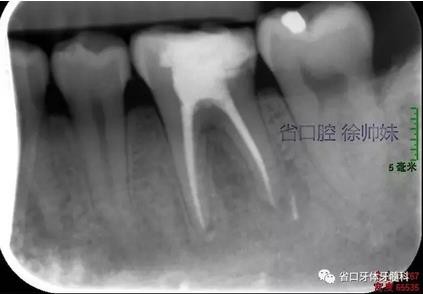

處理:36橡皮障隔濕,顯微鏡下去除封藥,沖洗根管,超聲蕩洗,熱牙膠連續(xù)波加壓充填根管(AH-PLUS),玻璃離子墊底,自酸蝕粘接,納米樹脂充填,調(diào)合,拋光。頰側(cè)牙周袋內(nèi)沖洗,置牙康。根尖片(圖3)顯示恰填,囑勿用患牙咬硬物,定期復(fù)查。

圖3 根充片